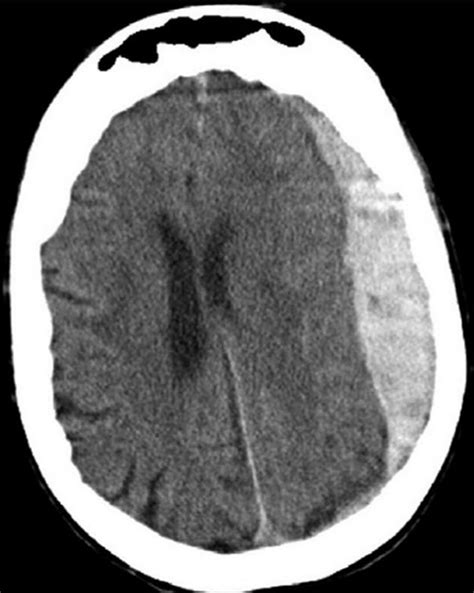

La diagnosi degli ematomi intracranici si basa di solito sui risultati della tomografia computerizzata (TC).

La TAC dell’encefalo consente di localizzare l’ematoma extradurale che si presenta come una lente biconvessa iperdensa.

La TAC evidenzia una sorta di “focaccia” che comprime un emisfero cerebrale e determina un importante effetto massa sulle strutture mediane.

La TAC evidenzia una raccolta ipodensa sottodurale con effetto massa sulle strutture mediane.